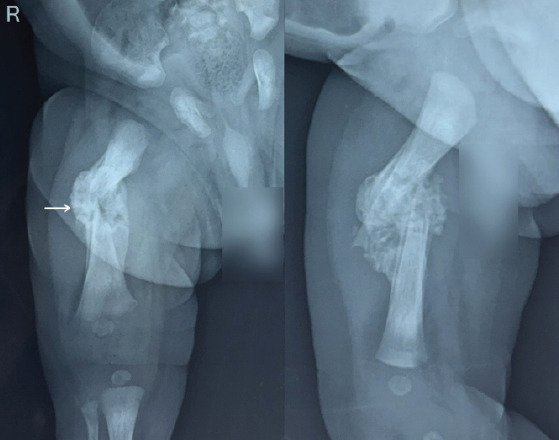

Case report: A 3915 g male child born at 38 weeks and 4 days of gestation to a primigravida aged 31 years by emergency Lower Segment Cesarean Section for Premature Rupture of Membrane with breech presentation. During extraction, the newborn sustained a fracture to his right femur shaft. X-rays confirmed the diagnosis. The fracture was treated successfully with a toe-groin cast for 25 days with complete healing.